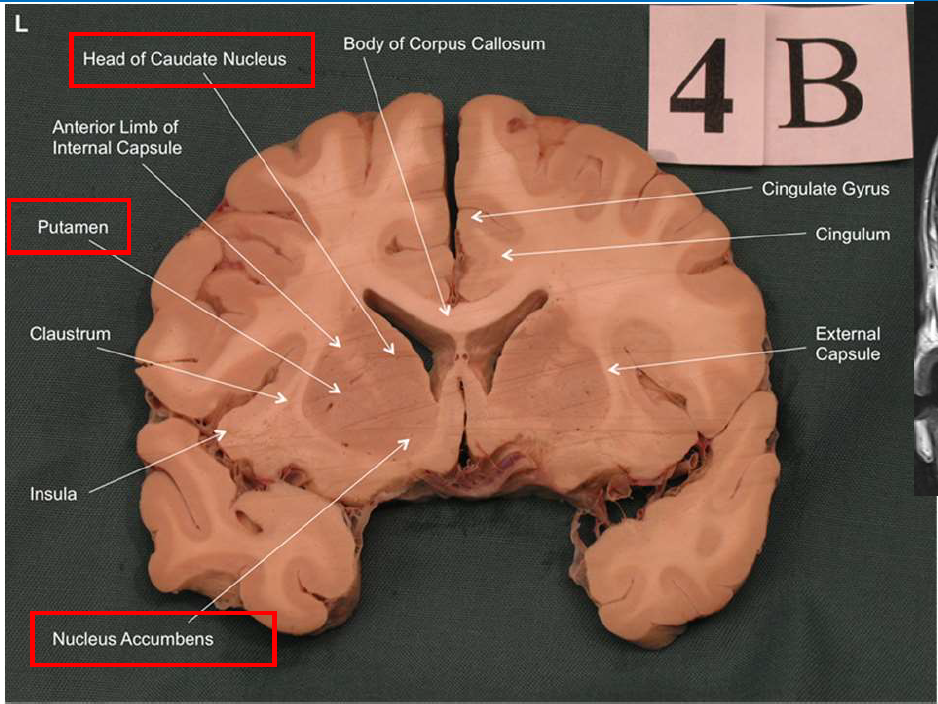

What structure is the major input to the basal ganglia?

striatum

What is the function of the nucleus accumbens (ventral striatum)?

Plays a major role in the brain's reward system, motivating us to seek pleasurable experiences.

Lesion → anhedonia